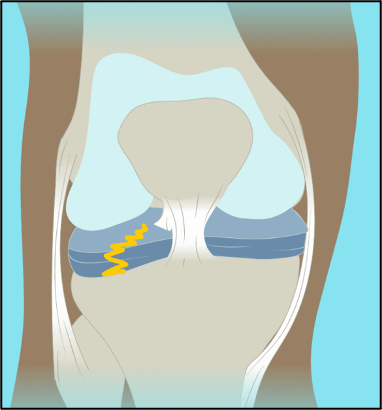

前交叉韧带是膝关节内重要的稳定结构,膝关节又是全身负重最大的关节之一。全身的体重都压在这个关节,尤其是在活动时。当 前交叉韧带损伤后,由于关节内特殊的情况(去纤维蛋白原的作用),关节内损伤组织并不能形成血肿,因此无法愈合,最终的结果是韧带慢慢就被吸收了(2个月以上)。

导致半月板损伤

导致软骨损伤

失去了前交叉韧带的关节,前后以及旋转不稳定,关节总是晃来晃去,必然导致关节内其它结构,如半月板,软骨的磨损,不仅在运动时反复扭伤,而且在日常生活中也会不断地磨损着关节,导致关节退变,也就是机器老化。